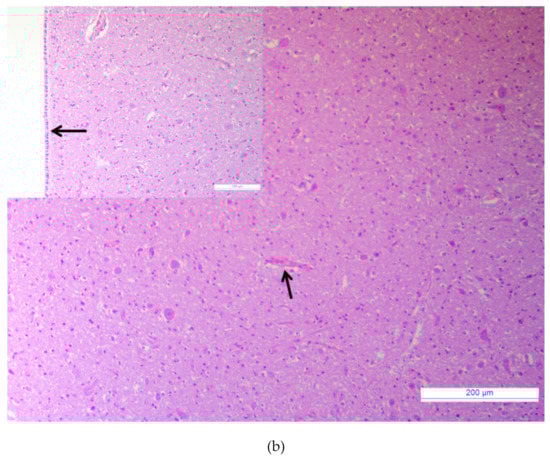

3.1. Major Neurotropic Pathogens Were Absent and Acute Non-Suppurative Encephalomyelitis Was Evidenced